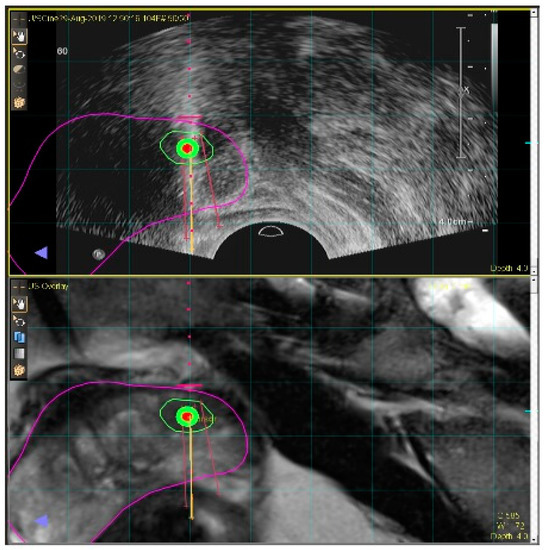

2.3.1. MRI–US